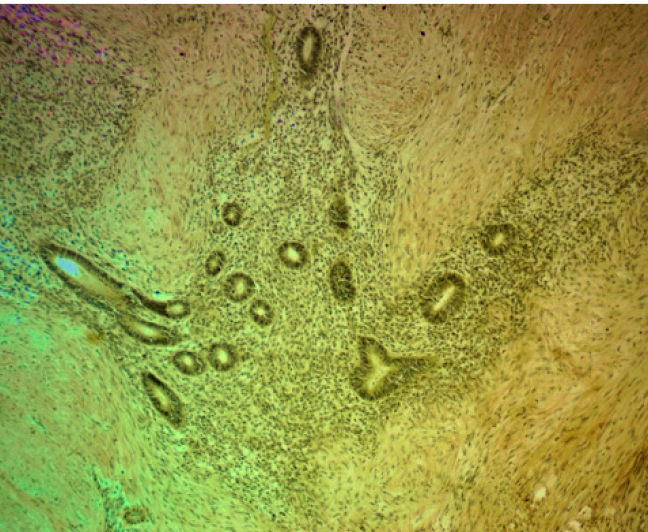

Очаговая экспрессия α-SMA была обнаружена в цитогенной строме очагов экстрагенитального эндометриоза в концентрических пролифератах миофибробластов по типу микроскопических лейомиом. В мышечном слое кишки наблюдалась положительная экспрессия α-SMA, которая повторяла ход мышечных волокон, деформируя стенку кишки в местах локализации очагов эндометриоза (рис. 4).

В цитогенной строме эндометриоидных гетеротопий и в соединительно тканных пролифератах была обнаружена положительная экспрессия трансформирующего фактора роста β-1. Площадь его экспрессии варьировала в разных наблюдениях от 10 до 15 % для цитогенной стромы и от 15 до 25 % для перифокально расположенных полей соединительной ткани (рис. 5).